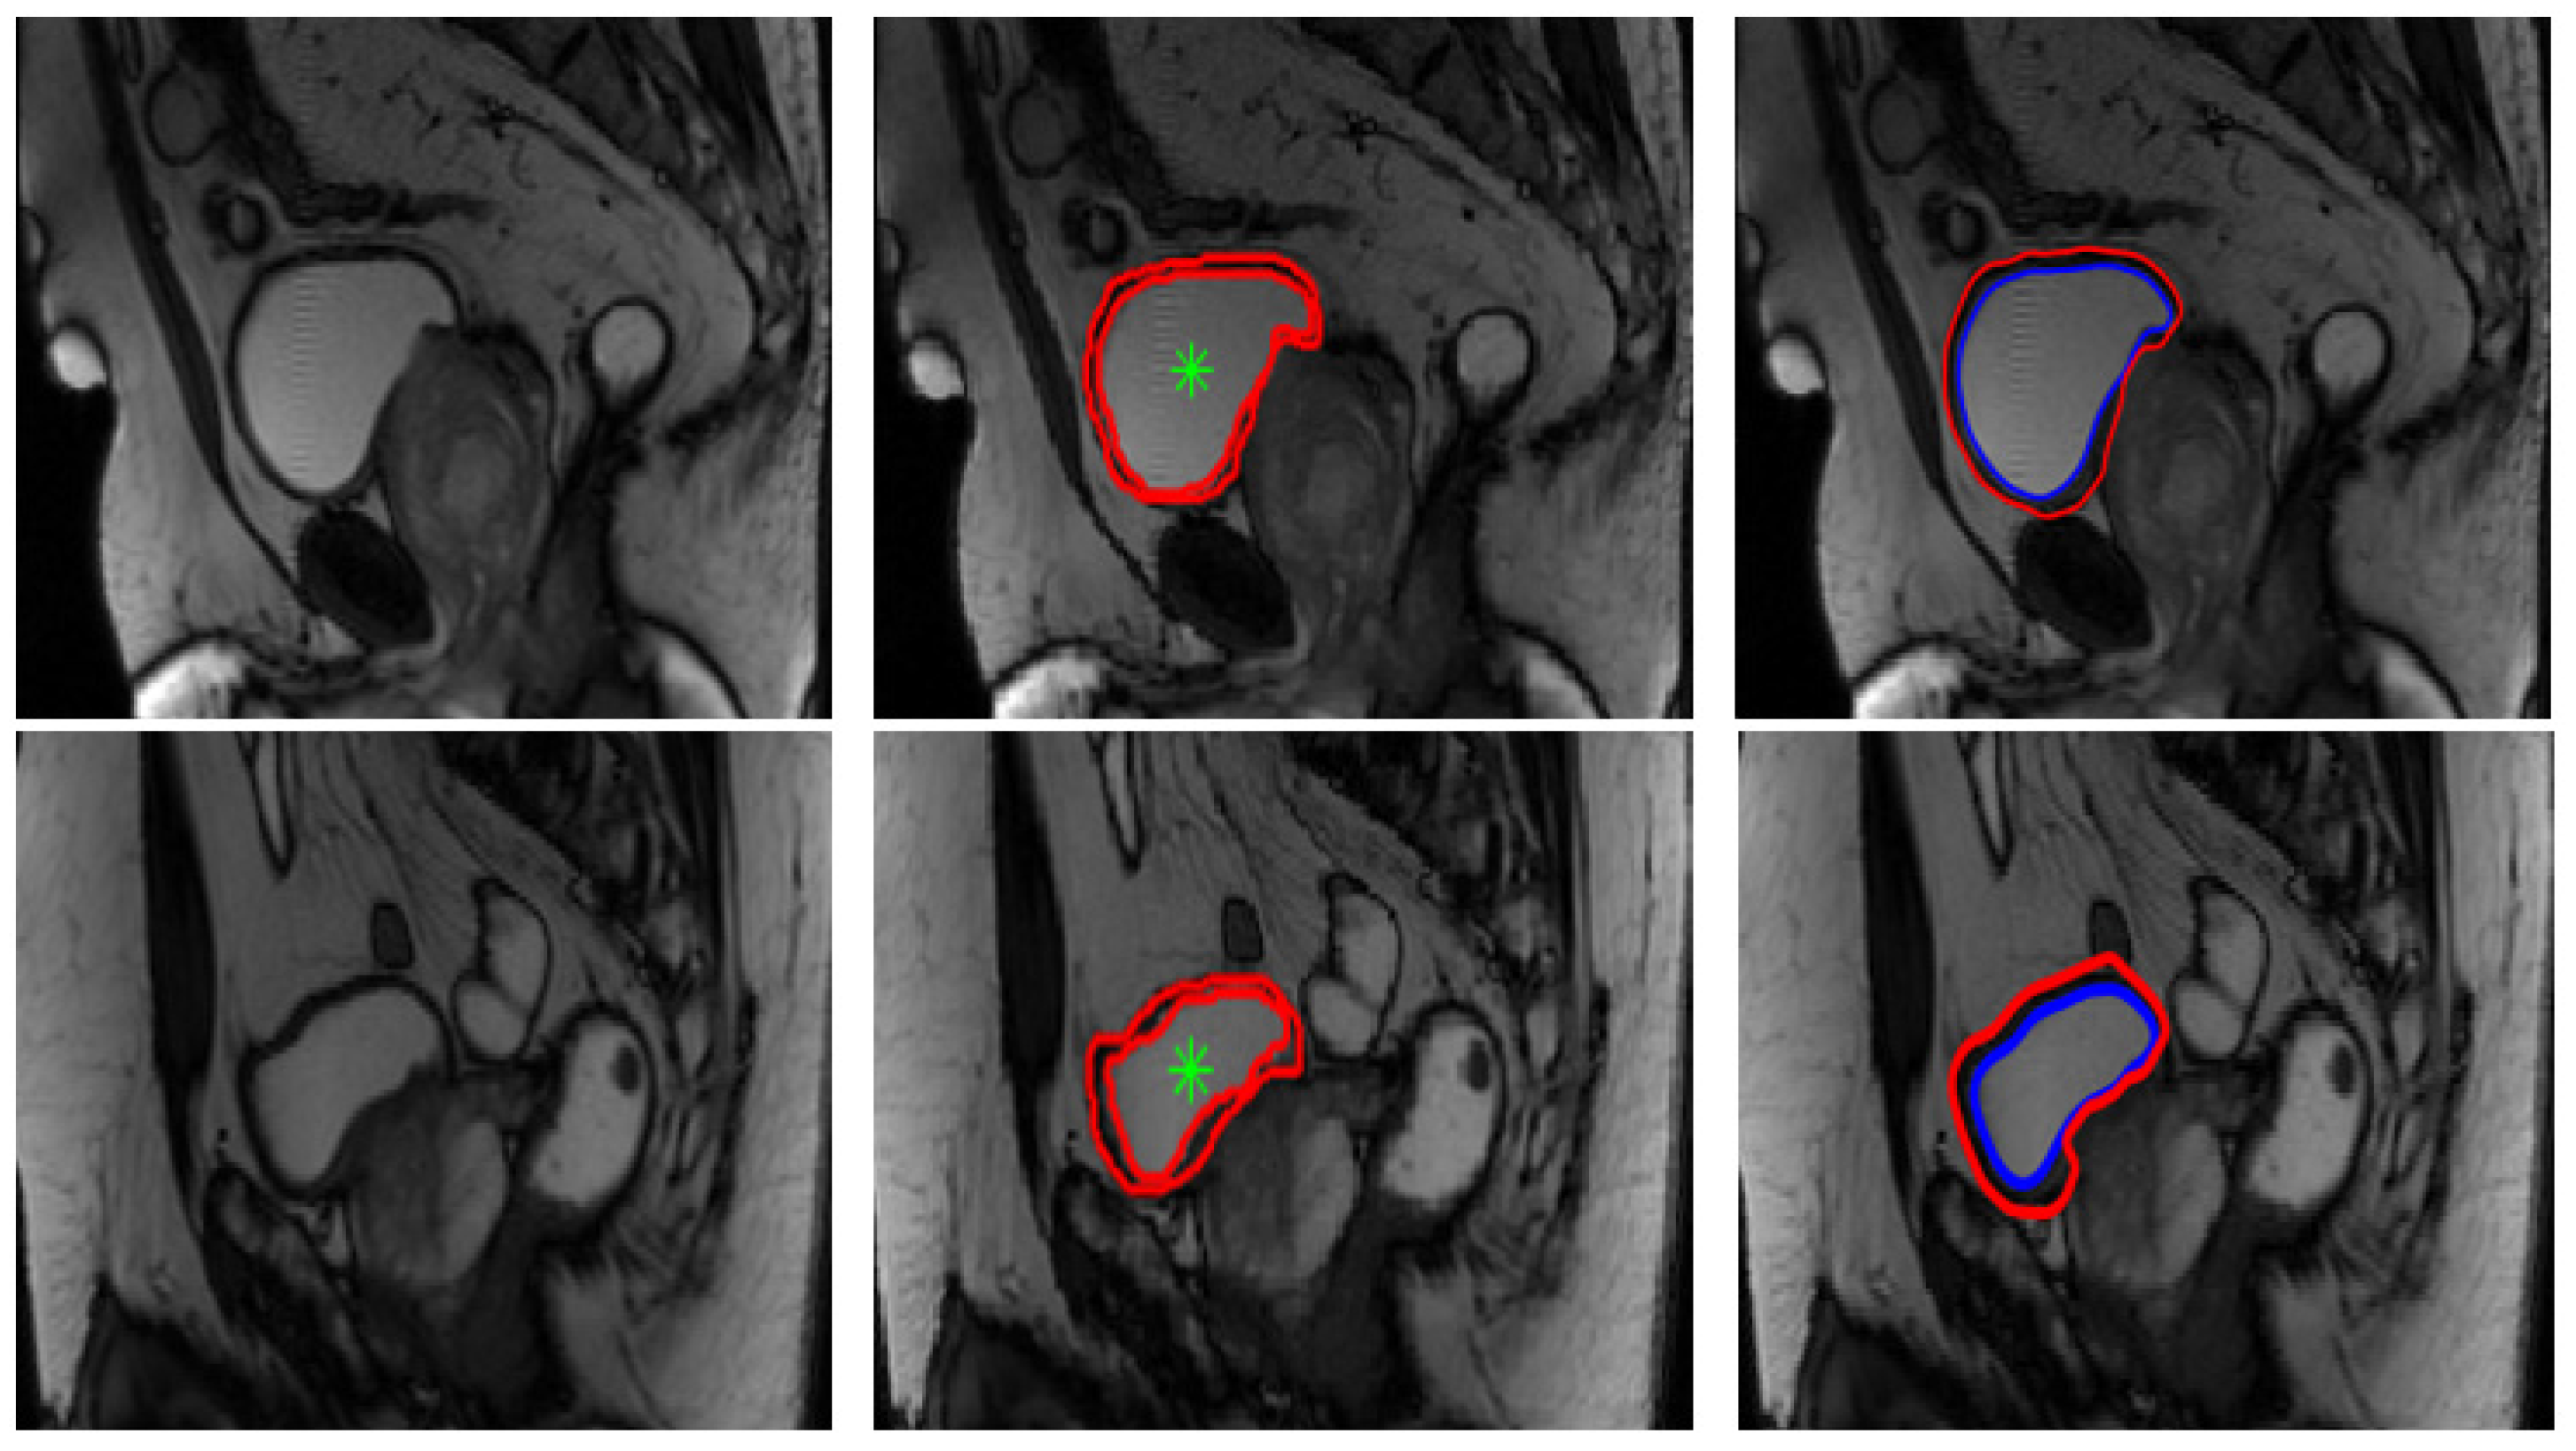

Segmentation results on our database were considered satisfactory by the medical team (some examples are presented in Figure 7 below). Manual segmentation considered as a ground truth was done by the medical team using a matlab algorithm that we have developed to be used by radiologists in our laboratory. As medical image segmentation is a crucial preprocessing step, comparing the quality of the semi-automatic segmentation with ground truth is an essential part. Therefore, in order to get a statistical validation, we have computed some metrics usually used for evaluating medical image segmentation, namely, Dice coefficient (DICE), mutual information and mean overall error rate, as shown in Table 1 below. The mutual information between two random variables [40] is defined as the measure of dependency between them. The Dice coefficient [41], called the overlap index and described in Equation (12), is the most used to validate medical segmentation:

Figure 7.

Examples of bladder wall segmentation results. Left column: original T2-weighted imaging. Middle column: bladder wall expert manual segmentation. Right column: Proposed Level Set approach segmentation results.